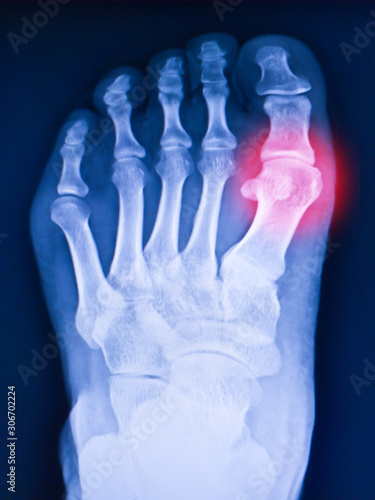

Болезни суставов: артрит подагрического типа на рентгене 1 пальца